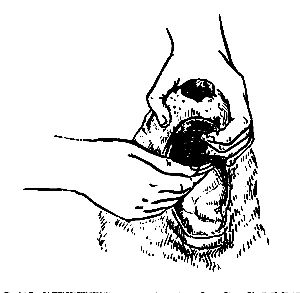

Большинство собак хорошо плавает и любит это делать, однако иногда животное может захлебнуться и утонуть. В этом случае прежде всего необходимо очистить нос и пасть животного и осторожно вынуть его язык, затем освободить легкие собаки от набравшейся в них воды. Для этого собаку берут за задние лапы и осторожно раскачивают взад-вперед. Если дыхание не восстанавливается даже после удаления влаги из легких, нужно сделать искусственное дыхание, сочетая его с непрямым массажем сердца. Собаку необходимо как можно скорее доставить к ветеринарному врачу.